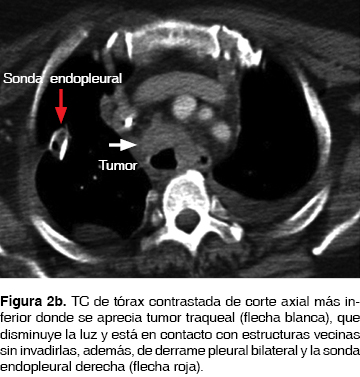

Su padecimiento actual lo inicio seis meses previos a su ingreso con disnea, estridor, con diagnóstico de asma por otra institución, tratada con broncodilatadores, esteroides, con mejoría parcial. La disnea progresó y el estridor en un inicio inspiratorio fue, posteriormente, bifásico con accesos de tos no productiva, con utilización de músculos accesorios para la ventilación. Ingresó al Servicio de Urgencias del Instituto Nacional de Enfermedades Respiratorias Ismael Cosío Villegas (INER), Ciudad de México, con datos de estenosis traqueal; motivo por el cual se le realizó broncoscopia flexible, observado tumor traqueal blanco nacarado, irregular (figura 1) desde el 2do. al 8vo. anillo traqueal (AT), 5 AT libres a la carina principal (CP) que ocasionaba disminución de la luz traqueal en un 90% y se dejó con intubación orotraqueal para permeabilizar la vía aérea. A los dos días le fue realizada una broncoscopia rígida con resección parcial de la tumoración para permeabilizar la vía aérea y toma de biopsia. En el posquirúrgico inmediato presentó enfisema subcutáneo en cuello, cara, tórax y neumotórax bilateral, colocándole sonda torácica bilateral. Por broncoscopia se identificó lesión traqueal, localizada en cara posterior en la unión con cara lateral de 1 cm de longitud a 3 cm de la CP, se dio manejo conservador con intubación orotraqueal ferulizando la lesión traqueal, con ventilación mecánica invasiva por siete días. El Servicio de Patología del INER reportó carcinoma adenoideo quístico. Para estadificarla se realizó TC de tórax (figura 2a, 2b), abdomen, pelvis y cráneo. Fue identificada la tumoración traqueal en tercio medio de la tráquea sin datos de lesiones a distancia. Se retiraron las sondas torácicas.